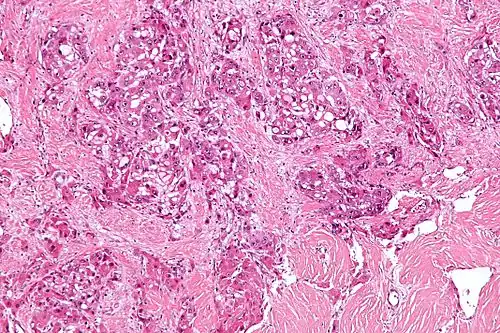

Micrograph of fibrolamellar hepatocarcinoma showing the characteristic laminated fibrosis between the tumor cells with a low NC ratio. H&E stain. | |

The histopathology of FLC is characterized by laminated fibrous layers, interspersed between the tumor cells. Cytologically, the tumor cells have a low nuclear to cytoplasmic ratio with abundant eosinophilic cytoplasm.[1] Tumors are non-encapsulated, but well circumscribed, when compared to conventional HCC (which typically has an invasive border).